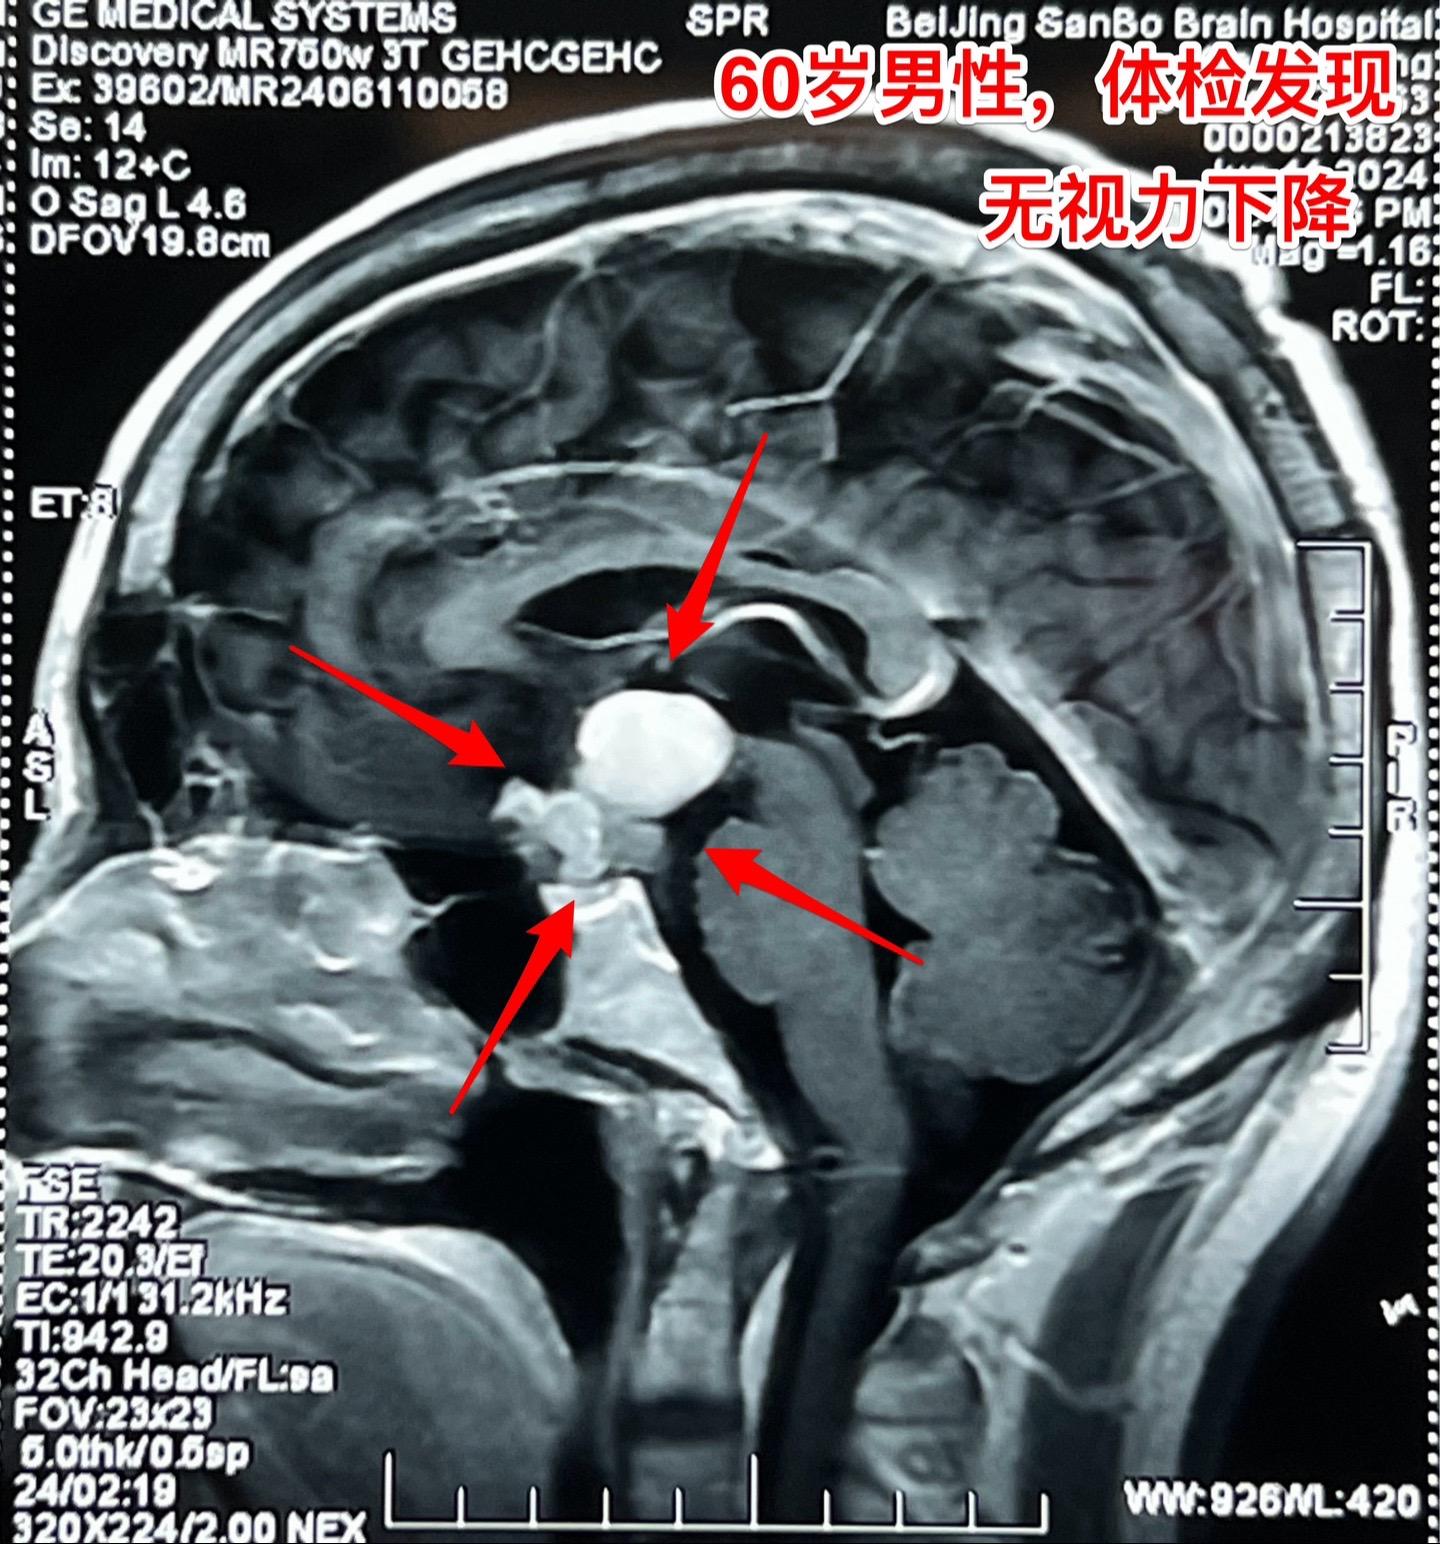

颅咽管瘤与拉克氏囊肿的鉴别不容易。60岁男性,偶然因头痛作体检发现鞍区肿瘤,怀疑为颅咽管瘤。病人无明显的视力下降。肿瘤体积不小了,CT也没有看见钙化。 到底是颅咽管瘤还是拉克氏囊肿? 2024年6月17日作了开颅手术。手术中看见病灶呈囊性,囊壁边界清楚,内有胆固醇结晶体,其周围脑实质有黄染。垂体柄得到保留。 手术后病理报告为:拉克氏囊肿。颅咽管瘤拉克氏囊肿